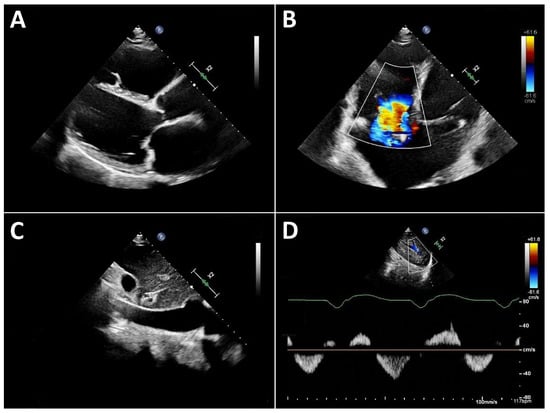

As noted above, left ventricular size should primarily be assessed using linear measurements. Implantation of a continuous-flow LVAD is typically associated with progressive left ventricular unloading and a corresponding reduction in ventricular size. While mean left ventricular end-diastolic diameter (LVEDD) reduction of approximately 1 cm has been reported, the magnitude of this change varies substantially between individual patients [7,10]. A substantial reduction in left ventricular diameter is often associated with a leftward septal shift and may occur in the context of excessive left ventricular unloading. Left ventricular function can likewise only rarely be quantified from apical views. Consequently, volumetric determination of ejection fraction as well as assessment of global longitudinal strain are usually not feasible. Therefore, linear measurements, such as fractional shortening, obtained from the parasternal long-axis view, are recommended. An even more accurate assessment, which is also frequently feasible, is measurement of left ventricular fractional area change in the parasternal short-axis view (Figure 1). Mild improvements in left ventricular function after LVAD implantation are frequently observed [7,10,11]. More substantial recovery of left ventricular function has been reported in a small but clinically relevant subset of patients [8,12,13]. In such cases, following comprehensive evaluation using dedicated testing and standardized weaning protocols, LVAD explantation may be considered.

Figure 1.

Parasternal short-axis view. Measurement of fractional area change (FAC) in a patient with an LVAD. (A): Planimetry of the end-diastolic area (EDA). (B): Planimetry of the end-systolic area (ESA). Calculation of FAC: FAC = (EDA − ESA)/EDA.